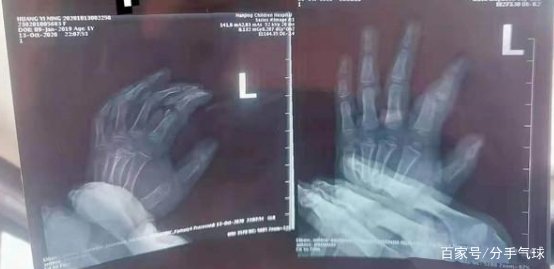

尹女士和她的丈夫带他们1岁的女儿出去玩。 李女士计划在南京市江北新区龙湖江北天街的一家奶茶店里买一杯饮料,所以给了女儿。 我的丈夫和张女士在休息区玩耍,而张女士正在点餐。 但是,尹女士的丈夫没有照顾女儿,而是在玩手机。 尹女士的女儿在商店里碰到了几张桌子。 当她无人值守地拉桌子时,桌子突然在力的作用下掉落了。 尹女士的女儿被压在桌子底下。 尹女士的丈夫发现自己的女儿被砸后,他立即跑来帮助她的女儿从地下。 尹女士听到女儿的哭声也跑过去了。 然后,丈夫和妻子将女儿送到医院,在医生的诊断下,尹女士的女儿左手食指受伤,并且跖骨近端粉碎性骨折。

为了治愈女儿的手指受伤,尹女士带女儿到南京和无锡的多家医院求医。 她还进行了两次手术,费用将近3万元人民币。 然而,即使在手术后,她的女儿也受伤了。 手指仍未愈合,可能需要移植。 尹女士说,由于女儿年纪轻轻,伤害评估要到2021年4月才能进行。女儿受伤后,尹女士和丈夫回到茶馆检查。 他们俩都发现伤病基本上是在桌子底下。 如果不加固,这些桌子重达十几公斤,容易倾倒。 尹女士和丈夫认为,奶茶店桌上的安全隐患使女儿受伤,奶茶店应承担责任,因此只提出了50万元的赔偿要求。